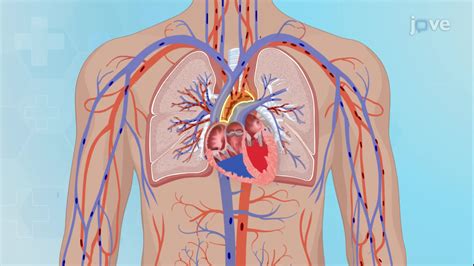

Learning that you or a loved one has a "leak" in the heart can be a frightening experience, often leaving more questions than answers. When a doctor uses this phrase, they are generally referring to a condition called valvular regurgitation, where one of the heart’s valves does not close tightly enough. To understand what is a leak in the heart, it is essential to first understand how the heart functions. The heart acts as a pump, using four valves—the mitral, tricuspid, pulmonary, and aortic valves—to ensure that blood flows in only one direction. When a valve fails to shut completely, blood leaks backward instead of moving forward into the next chamber or out to the rest of the body. This inefficiency forces the heart to work harder to maintain adequate circulation, which can lead to various health complications if left unmanaged.

To grasp the implications of a heart leak, imagine the heart as a house with four rooms and four doors. Each door is designed to swing open to let blood pass through and then click shut to prevent the blood from rushing back into the previous room. In a healthy heart, these valves open and close with precise timing and seal tightly. When a valve leaks, it is essentially like a door that doesn’t quite latch shut, causing a bit of air or, in this case, blood, to seep back through.